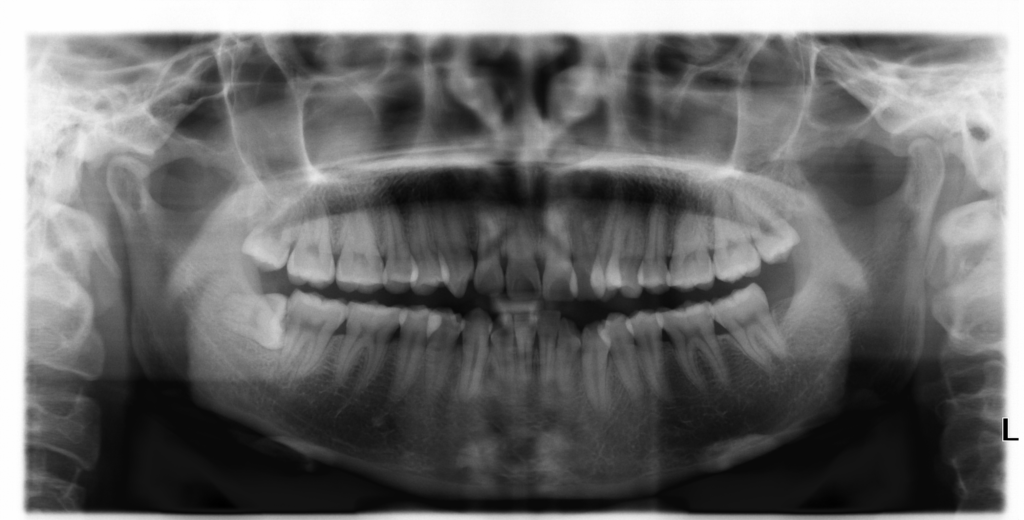

Em năm nay 23 tuổi, vừa rồi có đến phòng khám nha khoa để chụp phim xquang toàn cảnh và bác sĩ yêu cầu em nhổ 2 răng khôn mọc lệch. Nhưng hiện nay em thấy răng khôn không gây ảnh hưởng gì đến sinh hoạt cá nhân nên em không nhổ có được không?